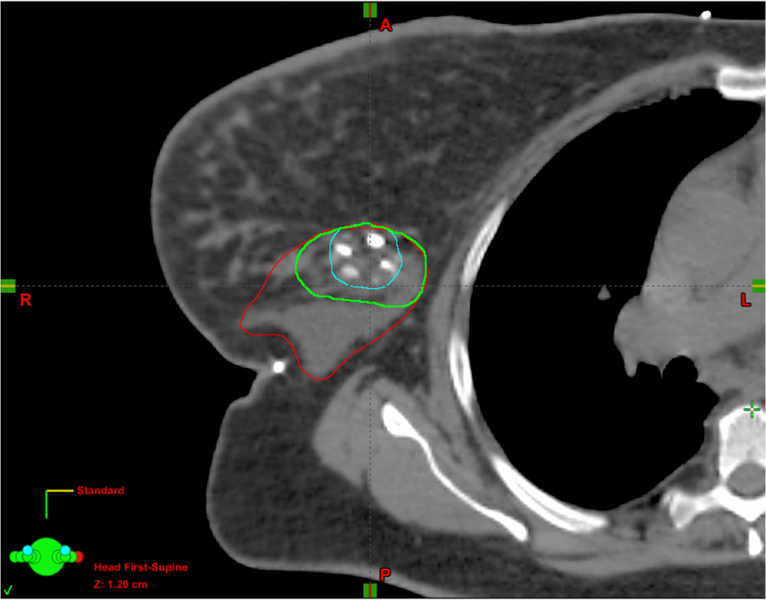

Radiation planning for breast cancer relies on accurate delineation of the post-lumpectomy target volume as identified ...